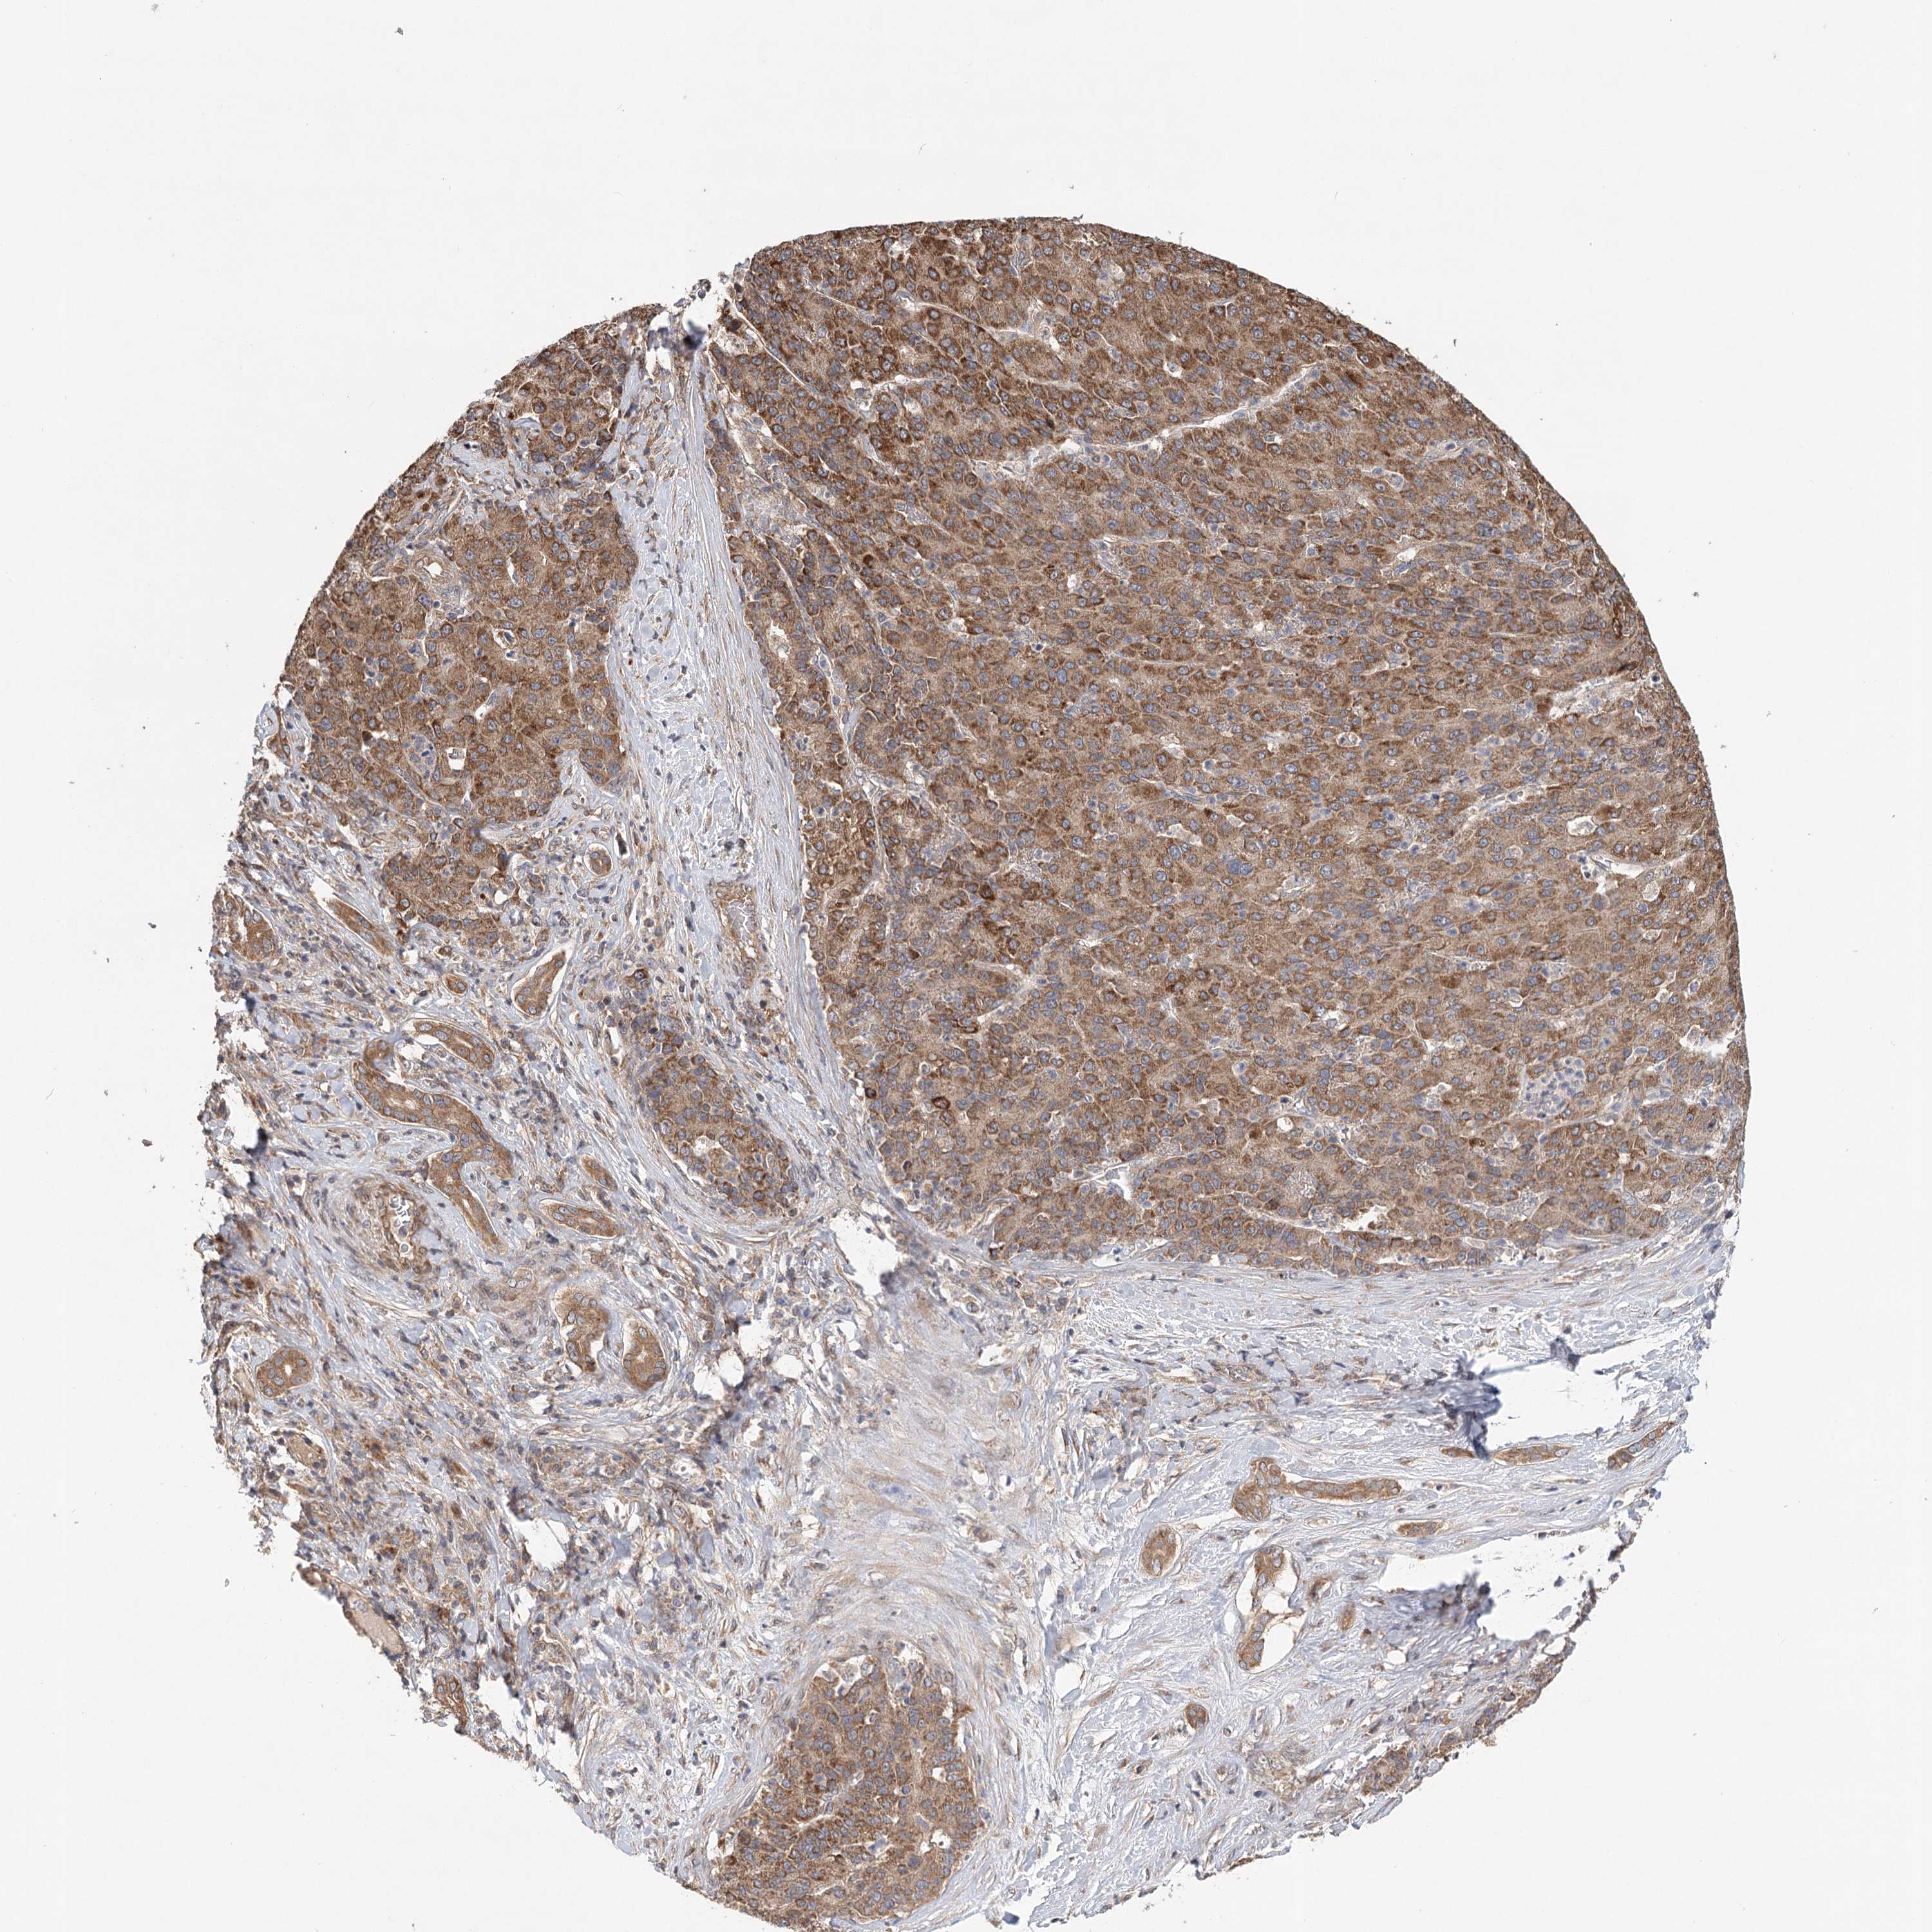

LIVER CANCER - Protein expressioni

A mouse-over function shows sample information and annotation data. Click on an image to view it in a full screen mode. Samples can be filtered based on level of antibody staining by selecting one or several of the following categories: high, medium, low and not detected. The assay and annotation is described here.

Note that samples used for immunohistochemistry by the Human Protein Atlas do not correspond to samples in the TCGA dataset.

Antibody stainingi

Antibody staining in the annotated cell types in the current human tissue is reported as not detected, low, medium, or high, based on conventional immunohistochemistry profiling in selected tissues. This score is based on the combination of the staining intensity and fraction of stained cells.

Each image is clickable and will lead to virtual microscopy that enables deeper exploration of all samples and also displays staining intensity scores, fraction scores and subcellular localization as well as patient and tissue information for each sample.

Antibody HPA032060

Antibody HPA032062

Antibody CAB034116

Staining

High

Medium

Low

Not detected

Intensity

Strong

Moderate

Weak

Negative

Quantity

>75%

75%-25%

<25%

None

Location

Nuclear

Cytoplasmic/membranous

Cytoplasmic/membranous,nuclear

Cholangiocarcinoma

Carcinoma, Hepatocellular, NOS